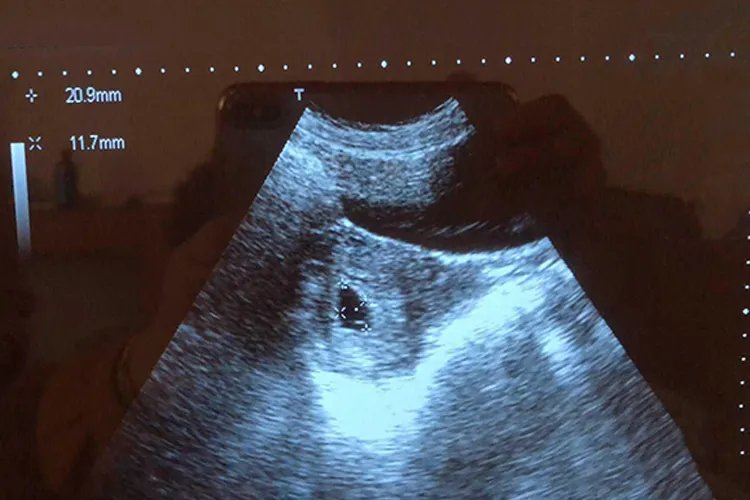

怀孕的时候可以出现许多生理变化,女性常感觉倦怠,乳房胀疼,或者胃口发生改变,月经推后,失眠或者尿频,排尿困难等。如果出现了上述的征象,可以用早孕试纸进行检测,一般的早孕试纸早七天、晚十一天,通过检测晨尿,可以检测是否怀孕,时间越晚,准确性越高。也可到医院进行抽血检查,通过抽血检查血HCG,可以检测是否怀孕,抽血检测HCG目前整个怀孕早期,也属于较准确的方法。同时可以进行B超检测,B超检测的时间比较晚,一般在孕五周或到孕六周的时候,到医院进行B超的检查,B超检查不但可以确定是否怀孕,还能够确定妊娠的位置在宫内或在宫外。